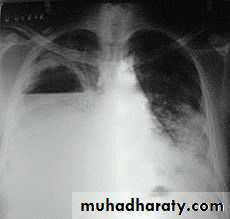

Pneumothorax

!! pneumothorax

Severe dyspnea with shock

Tension PneumothoraxTension Pneumothorax

Area of hypertranslucensy (pneumothorax)